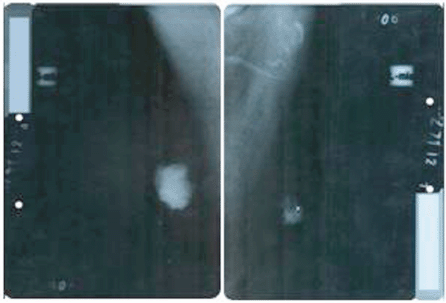

On performing the breast ultrasound, a solid, irregular lump was observed in RB, measuring 30 x 25 mm, of heterogeneous texture, with microcalcifications in its interior and adenopathies with a pathological appearance, while in the LB, a solid lump was observed, with a heterogeneous texture, measuring 22 x 20 mm, with irregular contours, located in the retroareolar region with no evidence of pathological adenopathies. The bilateral mammogram revealed the presence of a lump in the RB, with diffuse edges, infiltrates, measuring 40 x 35 mm, producing retraction and flattening of the nipple, with pathological microcalcifications in its interior, the spikes of the lump were close to the pectoralis major muscle, while in the LB, a lump was observed measuring 25 x 20 mm with diffuse spiked edges, with pathological microcalcifications both within and outside it (Figure 2). Both tests were classified, according to the Breast Imaging-Reporting and Data System (BI-RADS), as a category V lesion: highly suggestive for malignancy.

Figure 2. Bilateral mammogram: mediolateral oblique view showing the presence of lesions highly suspicious for malignancy, BI-RADS category V.